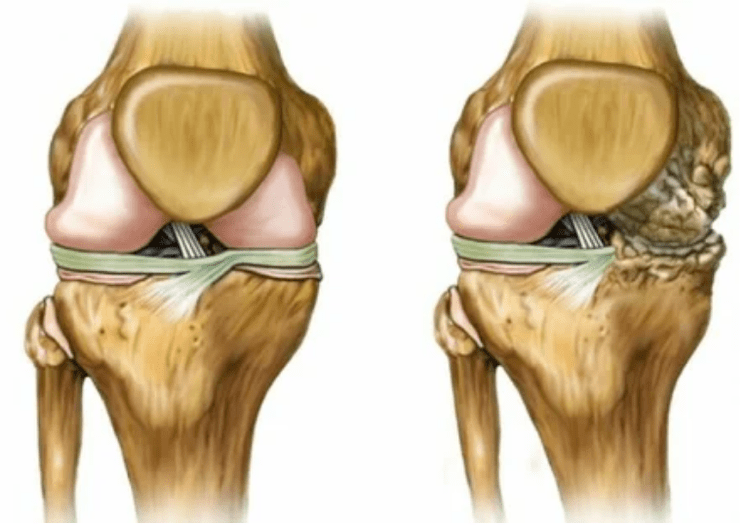

- Deformação articular, a cartilagem adquire uma forma irregular, provocando curvatura;

- Deterioração na condição do paciente com destruição completa da articulação.

Deformações dos membros. Aparece em uma forma negligenciada da doença, indica a destruição completa do tecido da cartilagem e o aparecimento de osteófitos. Nesse estado, a pressão nas juntas na parte superior e abaixo aumenta, a partir da qual a curvatura pode afetar todo o membro.